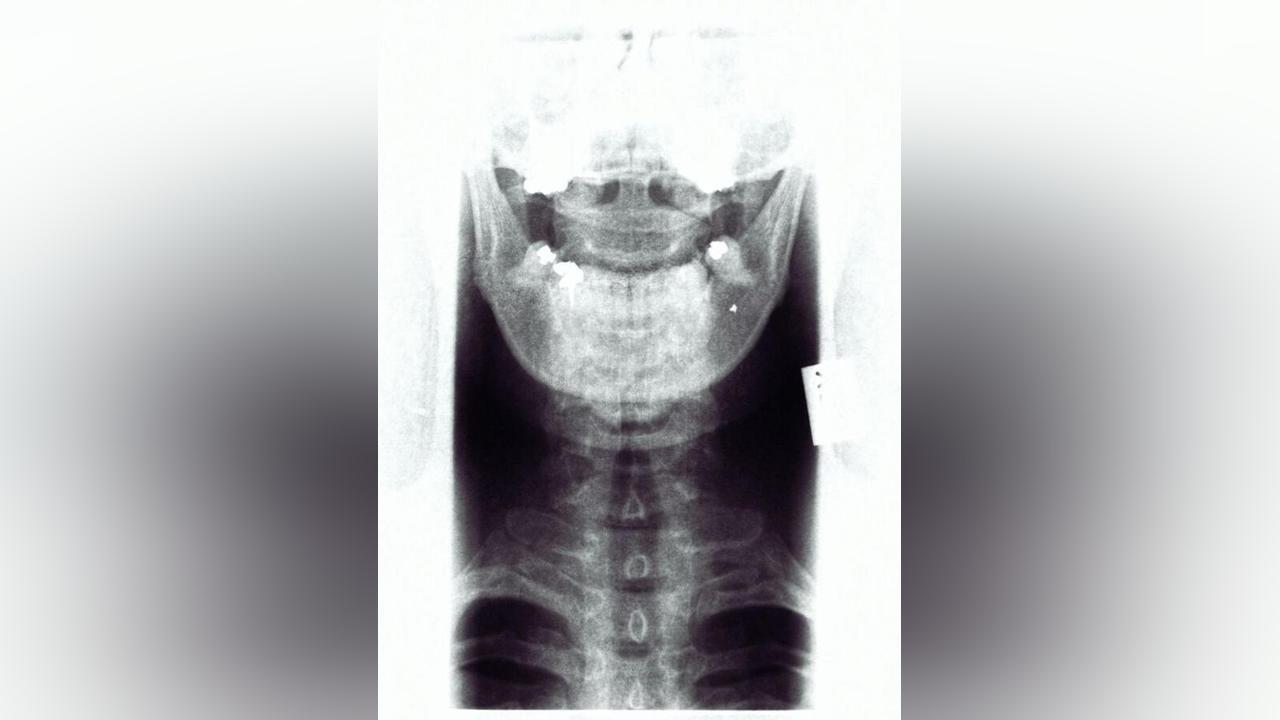

عندما سئل الرجل عن حالته، لم يكشف عن أي سبب محتمل لهذه الأعراض، لكن الأشعة المقطعية أظهرت جسمان غريبان داخل الجمجمة، يبرزان من أنفه إلى دماغه. وبعد الفحص الدقيق، تم التعرف على الجسمين على أنها عيدان تناول الطعام مكسورة.

عند سؤاله عن كيفية وصول عيدان تناول الطعام إلى جمجمته، كان المريض البالغ من العمر 35 عامًا في البداية في حيرة من أمره مثل أطبائه، لكنه تذكر لاحقًا حادثة كان متورطًا فيها قبل خمسة أشهر والتي يمكن أن تساعد في تفسير وضعه.

وبعد دراسة جميع الخيارات، قرر الفريق الطبي إجراء عملية جراحية بالمنظار من خلال الأنف، إلى جانب الجراحة المجهرية لإغلاق الناسور القحفي للمريض وإزالة زوج عيدان تناول الطعام المكسورة.